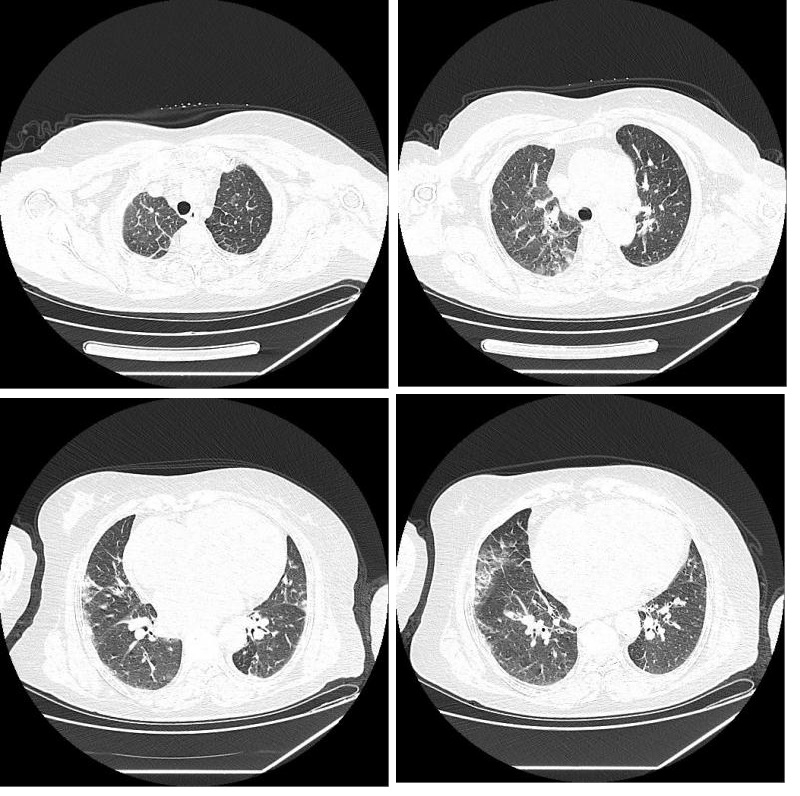

| 双肺小叶间隔增厚,双肺多发斑片影及磨玻璃影,双侧胸腔少量积液。心音增大,心包少量积液。肺动脉增粗 图 2 胸部CT |

核酸检测临床诊断存在假阴性,且检测时间较长,部分患者血或咽拭子核酸检测虽阴性,但仍不能完全排除新冠肺炎病毒感染,而CT检测时间短,方便快捷,CT结果提示罹患COVID-19时,可以做到早发现,早诊断,早隔离,早治疗,对于急诊患者尤为适合,所以建议把CT作为早期筛查新冠肺炎的一个非常有效地手段。新冠肺炎患者的CT影像学表现为:早期呈多发的斑片状磨玻璃影及间质性改变,以肺外带明显;进展期表现为病灶增多、范围扩大,磨玻璃影与实变影或条索影共存;重症期表现为双肺弥漫性病变,少数呈"白肺"表现,以实变影为主,合并磨玻璃影,多伴条索影以及空气支气管征。胸腔积液或淋巴结肿大等症状少见。该患者的胸部CT示双肺小叶间隔增厚,双肺多发斑片影及磨玻璃影,双侧胸腔少量积液。心音增大,心包少量积液。肺动脉增粗,该患者血常规提示淋巴细胞减少,而新冠肺炎患者淋巴细胞减少较常见[9],根据患者的辅助检查提示新冠肺炎不能排除,因此我们立即给该患者进行了核酸检测,结果呈阳性,由此可见,在没有流行病学史、呼吸道症状、血象及炎症指标没有提示新冠肺炎是,胸部CT可作为新冠肺炎的一个有效初筛手段。